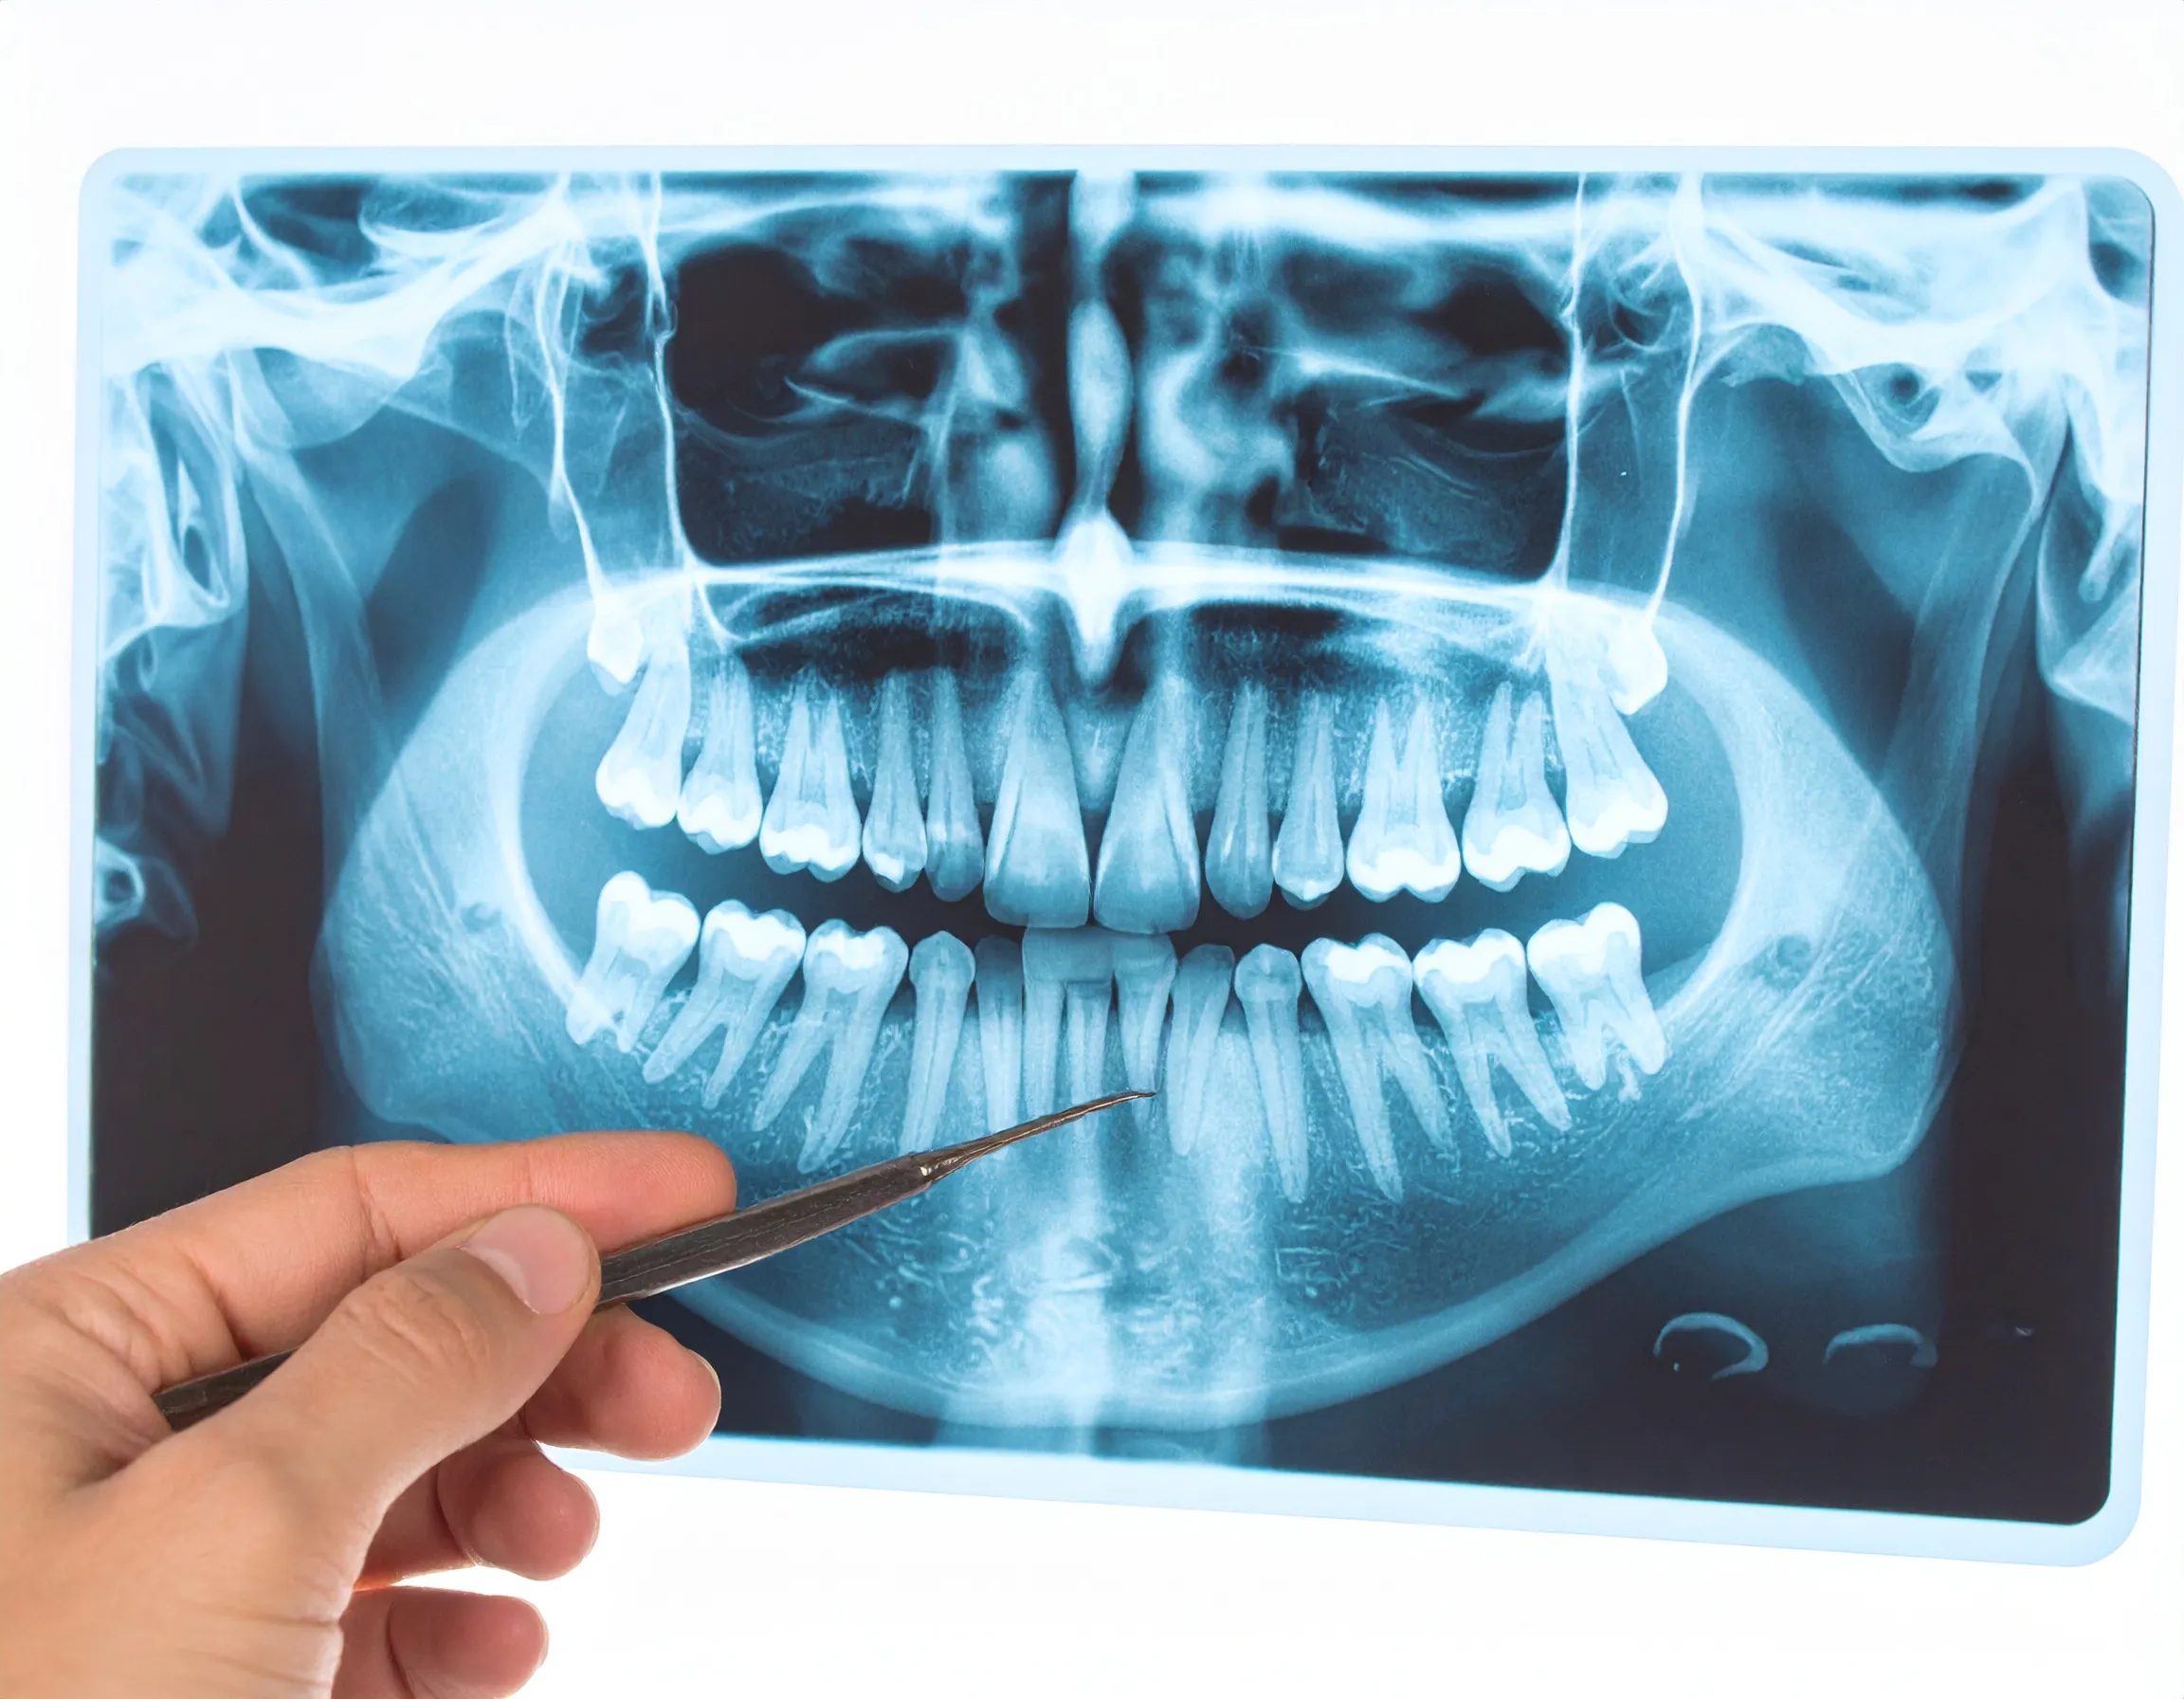

En illustration av en panorama-röntgenbild som granskas av en tandläkare.

Vid en vanlig undersökning kan vi se tandytorna, men en stor del av tanden och dess omgivning är dold för oss. Röntgenbilder är våra ögon in i dessa dolda områden. Utan dem skulle vi helt missa några av de vanligaste och mest allvarliga problemen.

• Bedömning av bennivån: Vid misstanke om tandlossning (parodontit) är röntgen avgörande för att se hur mycket av käkbenet som brutits ner.